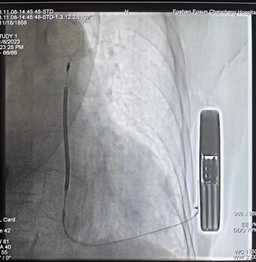

▲介入微创手术植入S-ICD

介入微创手术在介入手术室全麻下进行,保证患者安全与舒适。手术采用两切口植入,S-ICD的植入过程全程在皮下操作,无需穿深静脉,整个手术过程耗时约1小时,出血10ml,患者无明显痛感。术中除颤测试结果显示,植入很成功。

▲术中诱发室颤过程,S-ICD精准识别,65j一次成功转复

▲植入后影像